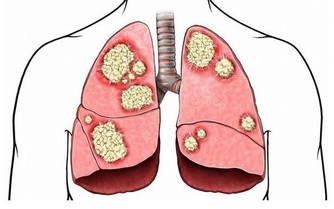

肝硬化發展到一定程度時易出現肝腹水,也就是腹中有太多積水,從而造成腹脹,導致放屁增多,以至於一天的排便次數大於10次。放屁次數跟肝硬化嚴重程度成正比,肝硬化病情越嚴重,放屁次數就越多。患有慢性肝炎、脂肪肝或酒精肝、長期服用藥物者,若放屁突然增多,還需及早去醫院做肝臟相關檢查,排除肝硬化的可能。

哪些行為可誘發肝硬化?

1、超重或肥胖

超重或肥胖者體內堆積太多脂肪,脂肪在肝臟中完成代謝,超出肝臟所承受的範圍,剩下的脂肪勢必會在肝細胞周圍堆積,從而導致肝細胞不能從血液中攝取營養,這裡面的代謝廢物也排不出體外,從而誘發脂肪肝。單純性脂肪肝並不可怕,適當地做好生活調理即可,但一直我行我素會逐漸發展成脂肪性肝炎,最終過渡到肝硬化或肝癌階段。因此應控制體重,從增加運動量和飲食方面入手,必要時還需借助醫學來減肥。

4、飲食太節儉

夏季天氣不僅炎熱而且濕度大,食物儲存不當或儲存時間太長,易滋生黃曲霉毒素,其毒性很強,也有一定的致癌性,攝入過量可增加患肝硬化或肝癌等風險,飲食飲食方面不能太節儉。若食物表面顏色發生改變、有異味等應立即扔掉。

5、不合理的飲食結構

攝入太多熱量和脂肪、頓頓吃得很飽,可增加肝臟承受的負荷,因此應調整好飲食,以植物性食物為主,少吃碳水化合物和高糖分食物。